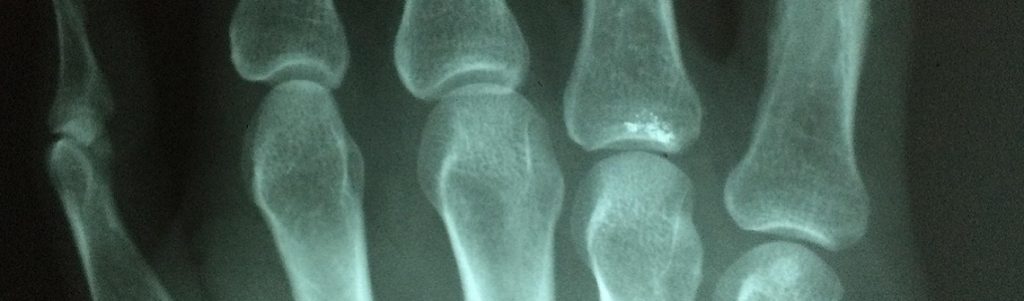

Les chercheurs ont réussi à prouver qu’il était possible d’obtenir de véritables os artificiels par impression 3D, avec ce matériau. Pour s’en convaincre, il suffit de regarder cette vidéo.

Dans le communiqué, Thomas Willet déclare ainsi « nous pouvons prendre des tomodensitogrammes et utiliser la conception assistée par ordinateur pour développer un modèle pour le morceau d’os qui doit être imprimé. »

Et il précise : « nous pourrions utiliser ce processus pour n’importe quel os qui a perdu un gros morceau ou qui a une géométrie complexe. »